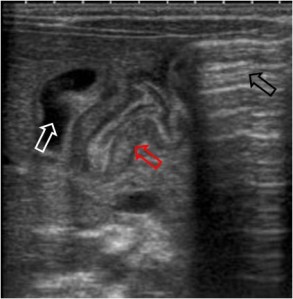

Imagen ecográfica de masa abdominal (tumoral, inflamatoria, invaginación intestinal,…) conformada por un anillo externo hipoecoico y una zona central hiperecoica, que recuerda al aspecto ecográfico del riñón.

La imagen muestra un pseudorrinón (a la derecha) en un niño con invaginación ileocólica.